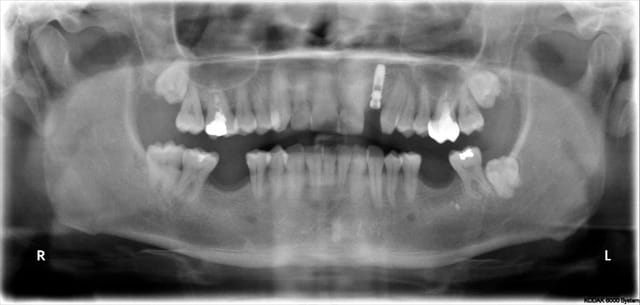

la première planif

grace à toi Béotien !

1 f9iy0w - Eugenol

2 dzt8ed - Eugenol

photo 1:on voit bien les collisions, tu as juste 2,5mm entre tes 2 implants

mais tu aurais du garder l'intégralité des dents pour avoir les racines

photo 2:pour l'implant en 16 c'est très bien

photo 3:pour l'implant en 15 j'aurais mis un 12x4,1

Photo 4:On voit bien avec les collisions que comme cela tu as plus d'espace entre les implants (j'ai enlevé la collision du tien)